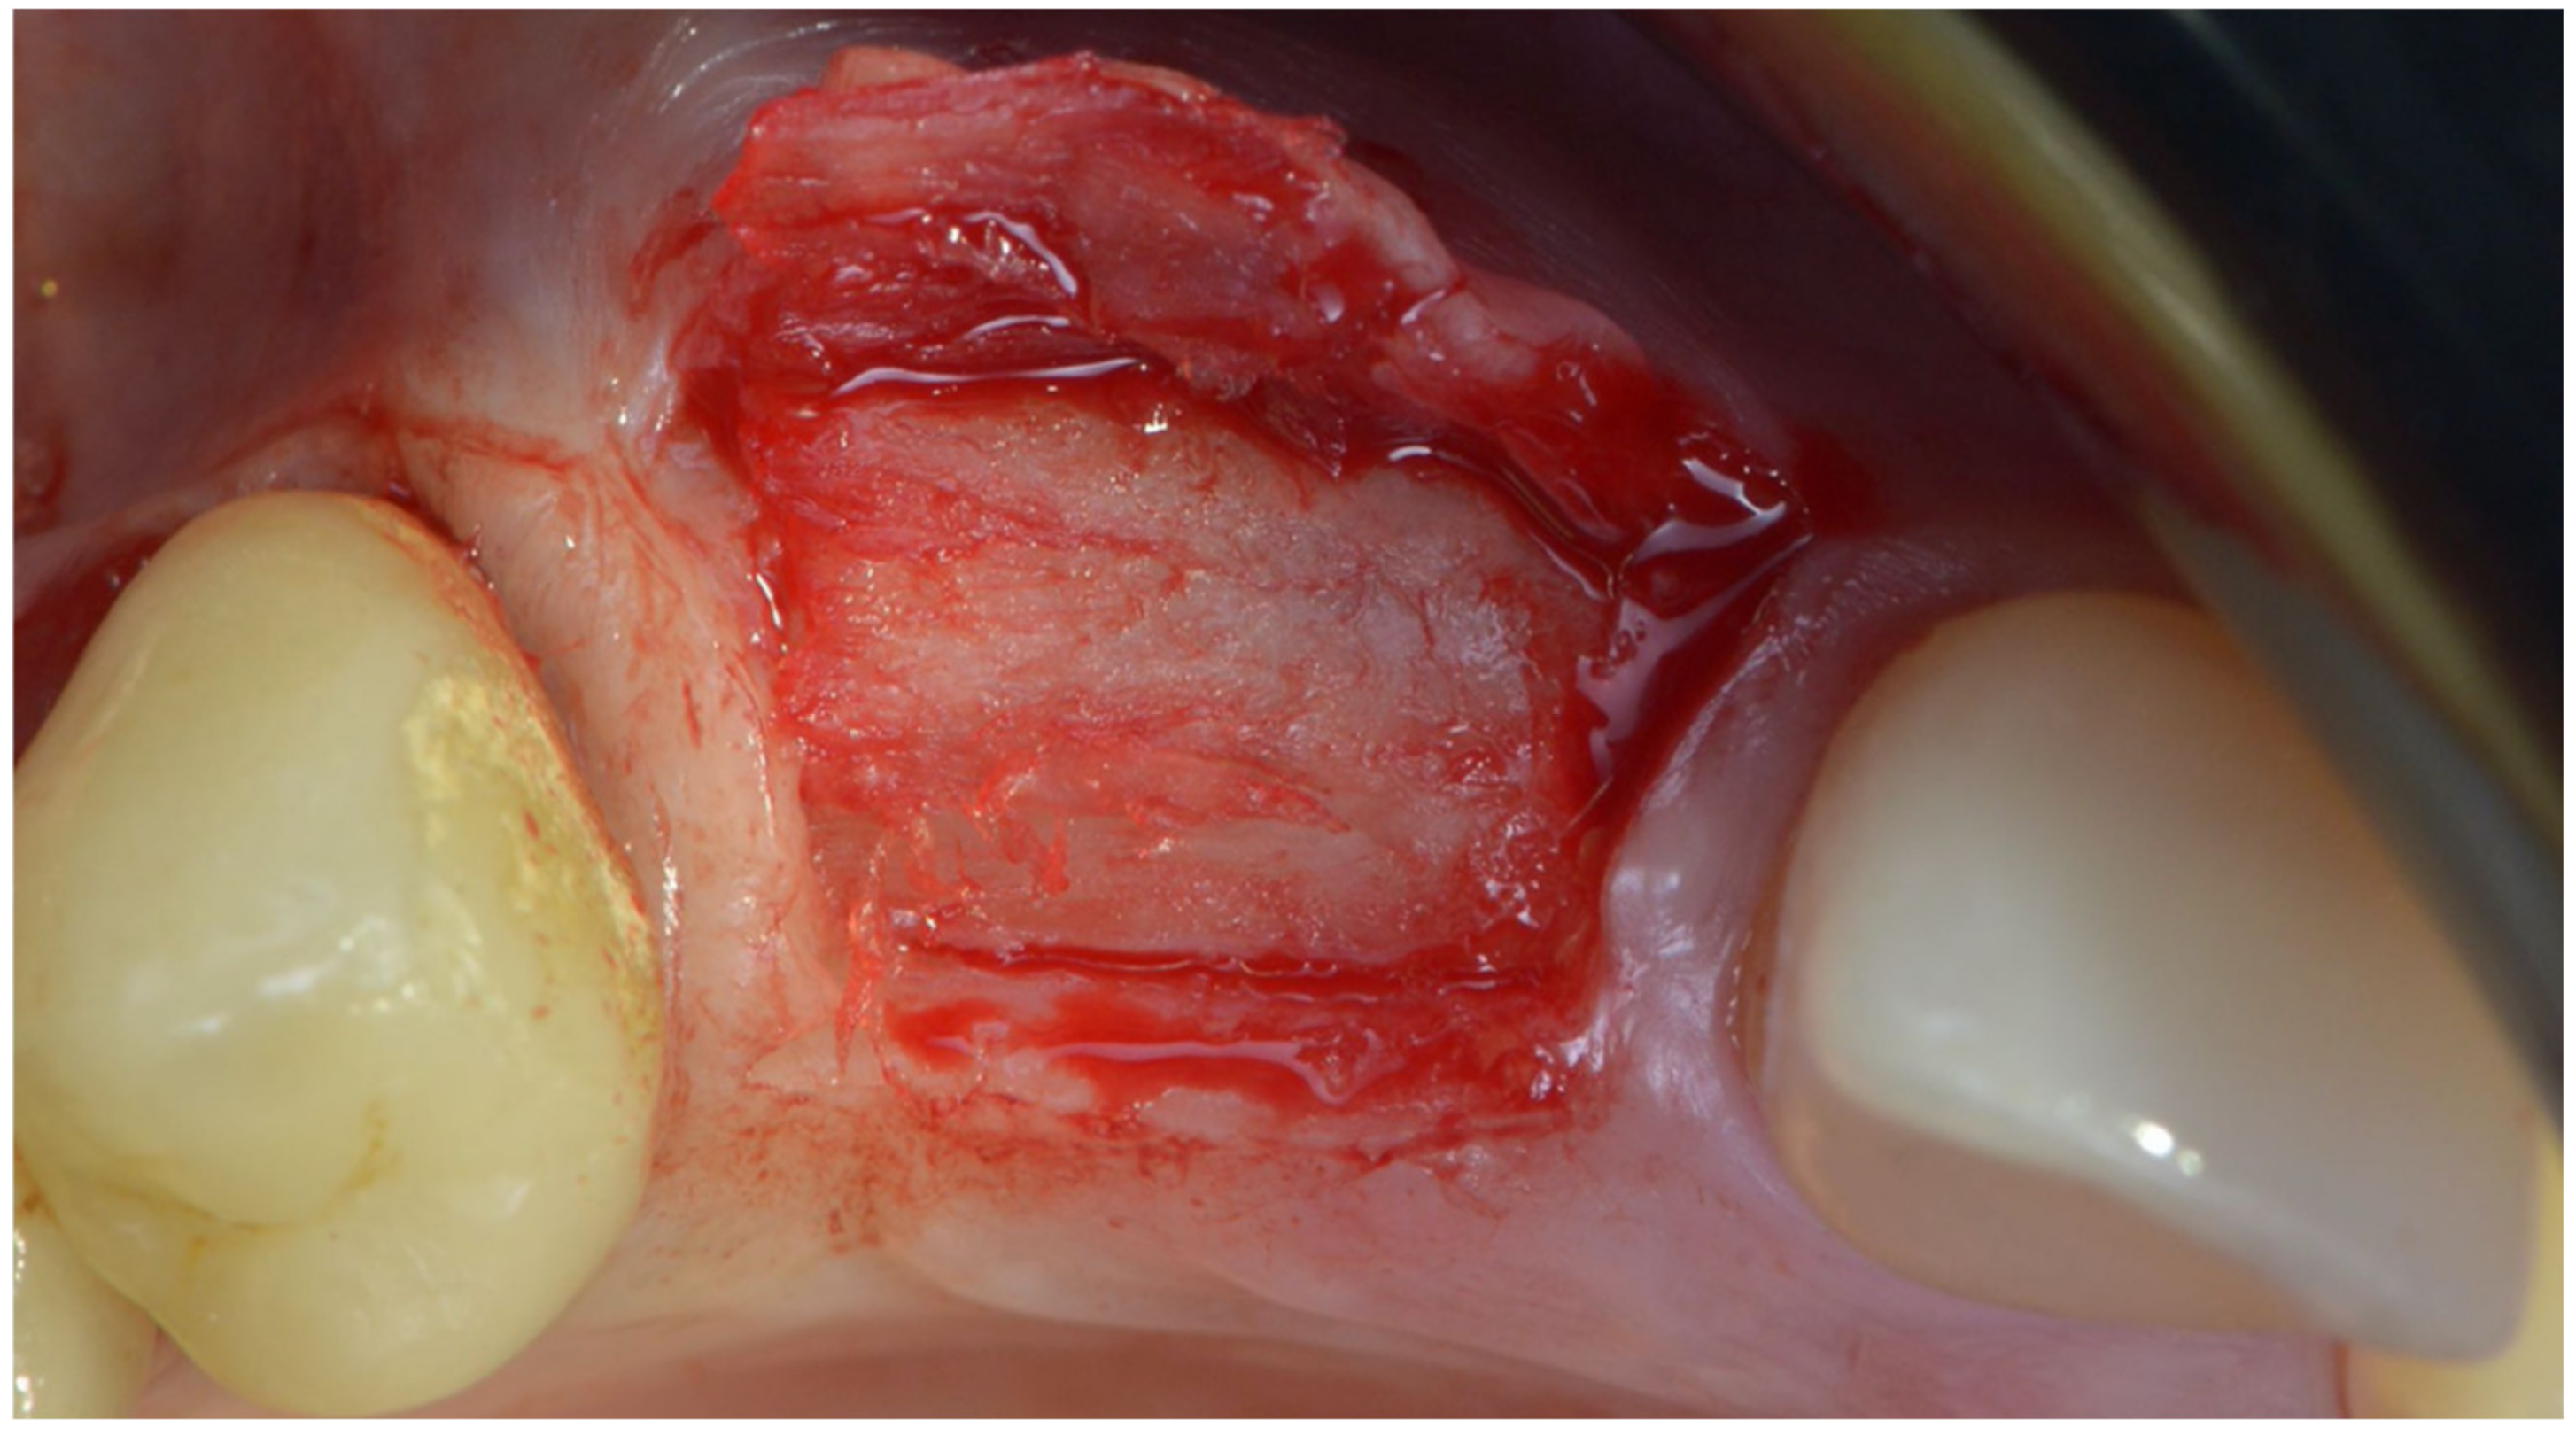

The site of 12 presented a very thin but visible buccal plate, while 11 had most of the buccal coronal aspect of the implant exposed. Some small holes were drilled into the buccal plate to produce some bleeding and with cells from the marrow spaces, while the area was augmented with a mix of autogenous bone scraped from the ramus and a collagenated xenograft. A bone lamina was cut and shaped in order to cover the graft and produce some horizontal and vertical augmentation of the area (Figure 15). We can see that some bone loss to the distal of 21 was also evident. Two pins were placed to the buccal apical aspect of the lamina to keep it firmly in place.

Figure 15.

The bone lamina stabilized to protect the two implants.